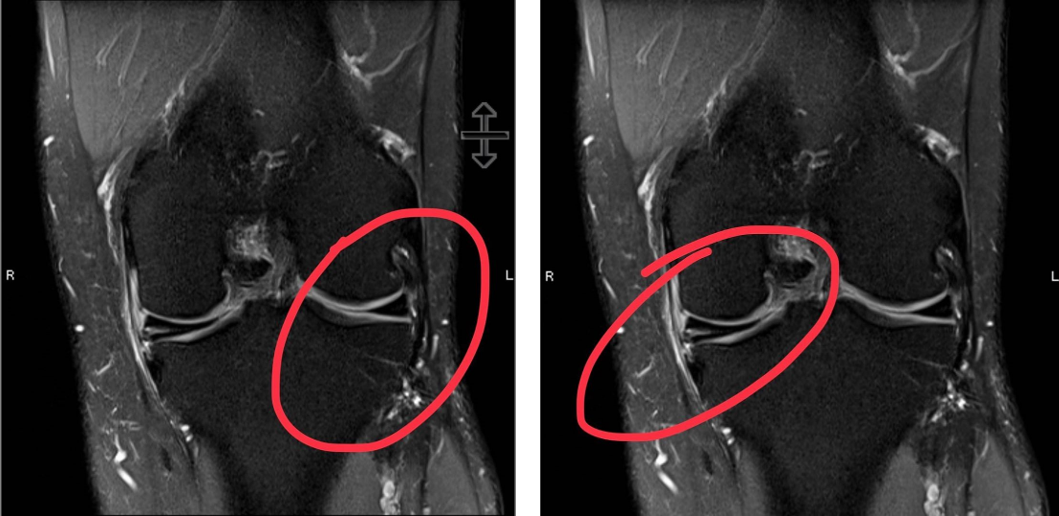

A torn meniscus can often be diagnosed via physical exam. The doctor will look for swelling, tenderness along the joint line, loss of motion, and pain with certain movements of the knee joint. An MRI can be used to confirm the diagnosis of a torn meniscus.